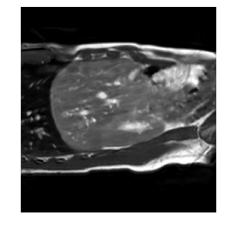

With this motivation, [6] proposed a convolutional neural network (CNN) based approach for temporal interpolation of navigators. Their CNN takes as inputs a fixed number of acquired images and learns to predict the missing images directly in the intensity space. This approach, which we call the Simple Convolutional Interpolation Network (SCIN), is a ’black-box’ formulation that does not incorporate any prior information about the interpolation process. Image prediction is guided only by the cost function used to optimize the network parameters. The issue with this is that it is unclear whether the image similarity measures that are generally used as cost functions suffice to ensure fidelity of the generated images to the original images. Indeed, Fig. 1b shows a case where an image interpolated using SCIN is quite blurry and misses several liver and lung structures present in the original image.

(a)                                (b)                                (c)

Figure 1: (a) Ground truth and (b,c) interpolated images from (b) baseline (SCIN) and (c) proposed method (MFIN). The image interpolated via SCIN is heavily blurred and misses several lung and liver structures, while the proposed method is able to preserve the details in the ground truth image.